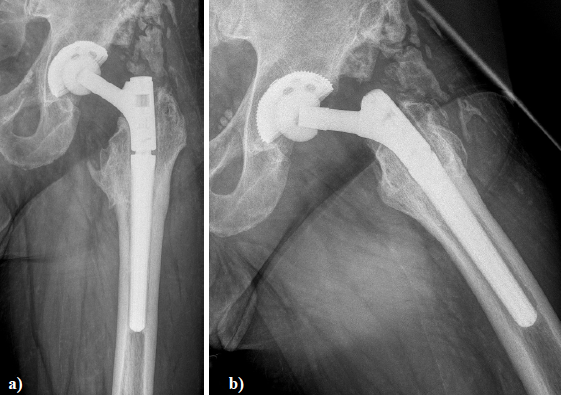

In August 2013 THA was performed due to a girdlestone situation after septic osteoarthritis of the hip (Figure 1) in a 46 year old male patient using a MRP Titan revision stem (Diameter: 18mm, length: 140 mm) (Peter Brehm GmbH, Weisendorf, Germany) and a cementless cup (Allofit - IT; Diameter 54 mm, Zimmer, Warsaw, USA) and a ceramic on ceramic bearing (head diameter: 36 mm) (Figure 2). The patient was 175 cm tall and weighed 105 kg (body mass index: 34.3 Kg/ m2). 2 weeks later revision surgery due to recurrent dislocation (Figure 3) was performed. Revision of the acetabular component was done using an Allofit - Classic- cup, Diameter 56 mm (Zimmer, Warsaw, USA)). The neck component was exchanged from small to medium size (Figure 4). A ceramic on PE bearing was implanted (head diameter: 32 mm). Postoperative healing was uneventful. The patient was out of any complaints. In February 2016 the patient started suffering from slight thigh pain but detected crepitation in the region of the left hip. X-ray of the left hip in 2 planes in May 2016 revealed an asymmetrically gap of the stem / neck junction (Figure 5). During revision surgery of the left hip breakage of the cone of the morse taper junction was visible (Figure 6). Removal of the well-fixed stem was performed via a distal fenestration. After fixation with cerclage wires a bended MRP Titan revision stem (Diameter: 19 mm, Length: 200mm with long neck and extension sleeve) was implanted using a 32 mm ceramic head (Figure 7). Postoperative healing was uneventful.

Figure 2. X - ray of the left hip in 2 planes: ap view a. and lateral; b. view shows THA using a MRP Titan revision stem with a short neck and a cementless cup.